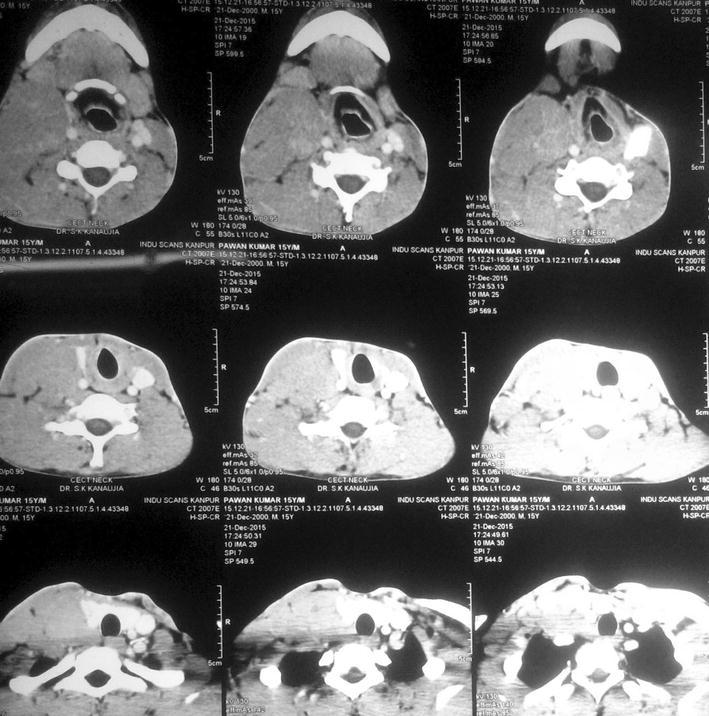

A fifteen year old boy was presented to our hospital with chief complaints of painless progressive swelling in the right side of neck in last 6 months. Patient was having no history of fever, pain in throat, difficulty in deglutition, difficulty in respiration, chronic cough, loss of appetite or loss of weight. On examination there was non-tender, non-fluctuant soft to firm swelling involving anterior and posterior triangle of neck about 10 × 6.5 cm in dimension on right side. It was mobile and not adherent to underlying skin (Figs. 1, 2). There was also swelling involving bilateral supraclavicular region. There was no any swelling in axillary or inguinal region. On nasal endoscopy no abnormality was detected. Routine haematological examination showed Haemoglobin 12.2 g%, Total leukocyte count 6.3 × 109/litre, Erythrocyte sedimentation rate 15 mm 1st hour while differential leukocyte count was with in normal limits. Mantoux test was negative. High resolution Ultrasonography suggested multiple discrete, homogenous lymph node in right carotid space. There was no cystic necrotization, calcification or loss of fibrofatty plane are seen (Fig. 3). Contrast enhanced computed tomogram neck with thorax suggested a large lobulated soft tissue lesion about 10 × 6.5 × 5.5 cm in dimension (Fig. 4). No intratumoral necrosis was seen. Patchy heterogeneous enhancement was seen in post contrast images. Mass was mildly compressing trachea and right thyroid gland to the left (Figs. 5, 6). Bilateral supraclavicular lymph node was seen along with non-necrotic lymph node in superior mediastinum. Fine needle aspiration cytology from cervical lymph node was highly suggestive of Rosai–Dorfman disease, however biopsy was advised for confirmation. Biopsy was done under local anaesthesia from the posterior triangle of neck just behind the mid part of sternocleidomastoid muscle. Histopathology showed diffuse effacement of lymph node architecture and dilated sinuses distended with benign histiocytes (Figs. 7, 8); the diagnosis was given as sinus histiocytosis with massive lymphadenopathy (Rosai–Dorfman disease). This patient was put on oral prednisolone 10 mg three times a day in tapering doses for 21 days initially and then on low dose of steroids for next 4 months. The patient showed marked clinical improvement.

Fig. 5.

CT scan axial view 1

Fig. 6.

CT scan axial view 2